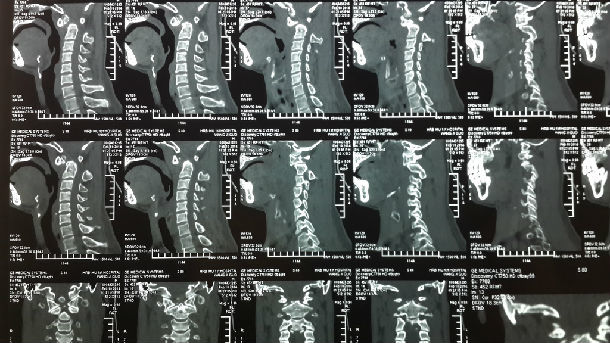

术前CT示寰枢椎脱位,ADI 大于5mm